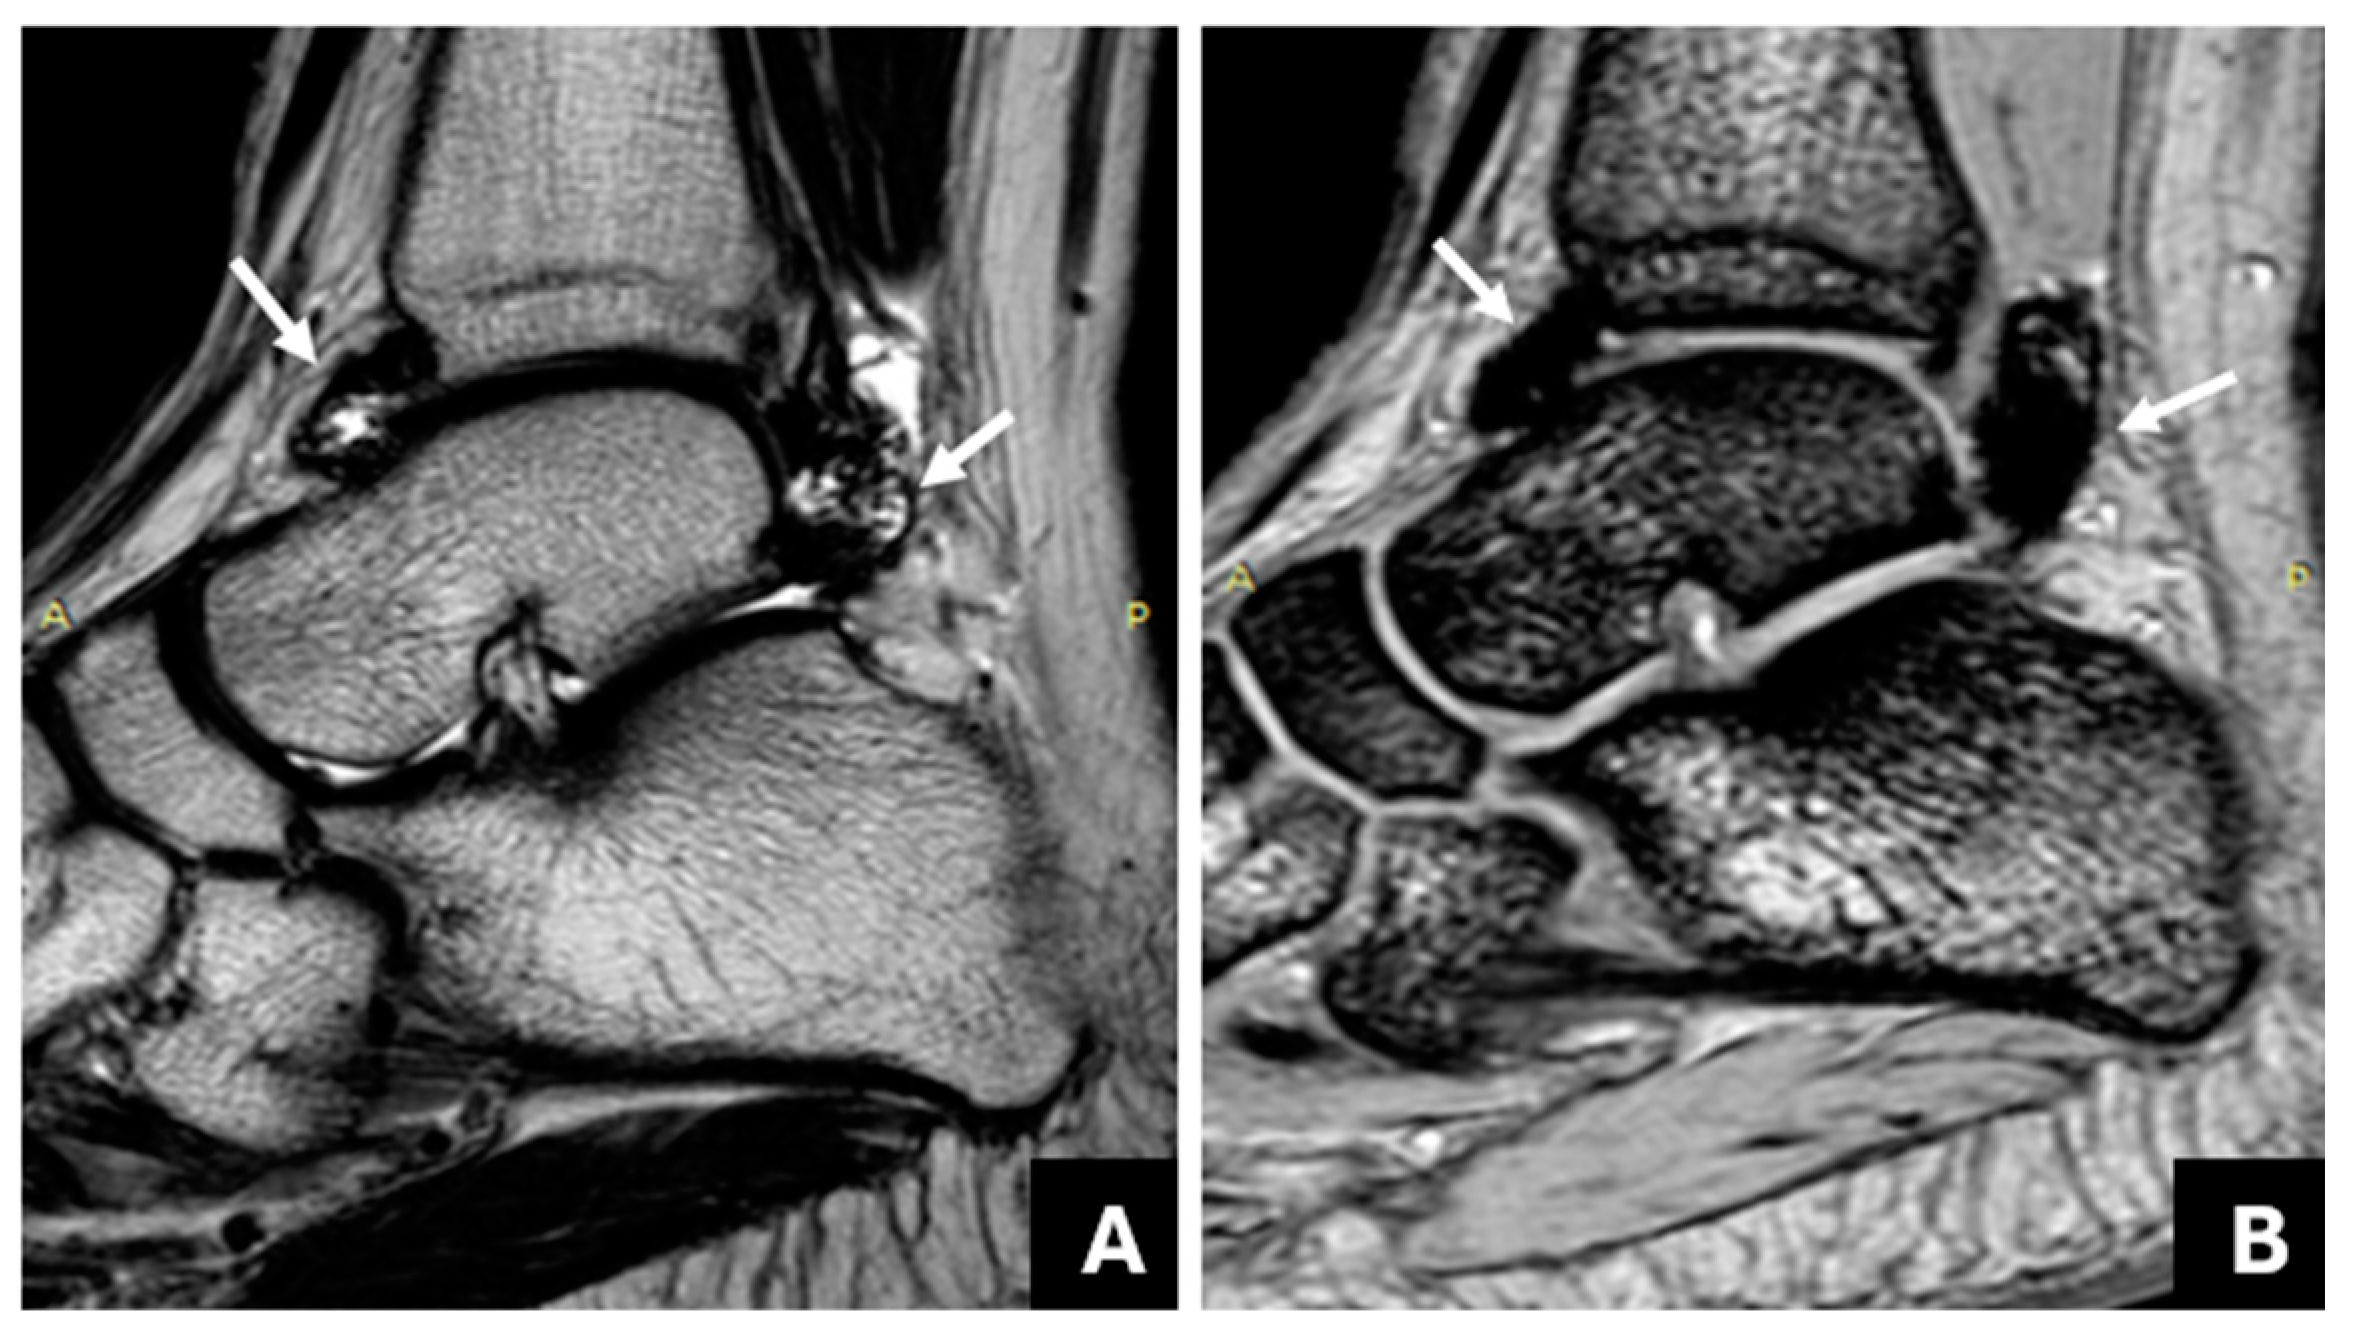

3.1. Detection of Joint Hemosiderin Deposition with mGRE Sequence: Inter-Reader Agreement

3.2. The Association of Joint Hemosiderin Deposition with Synovial Thickening, Effusion, and Osteochondral Changes (OCC)